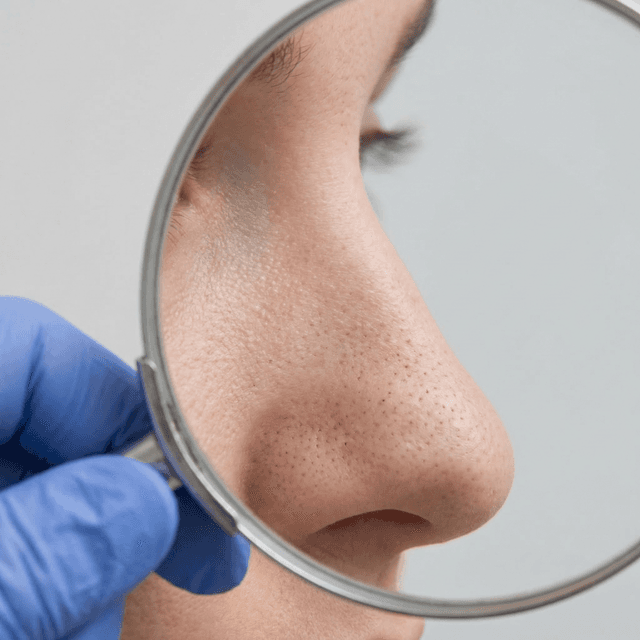

Blackheads (Open Comedones): Why They're Dark, How to Remove Them Safely, and What Actually Prevents Them

Blackheads aren't caused by dirt — they're oxidized oil plugs in open pores. Here's the science behind why they form and the dermatologist-approved ways to actually get rid of them.